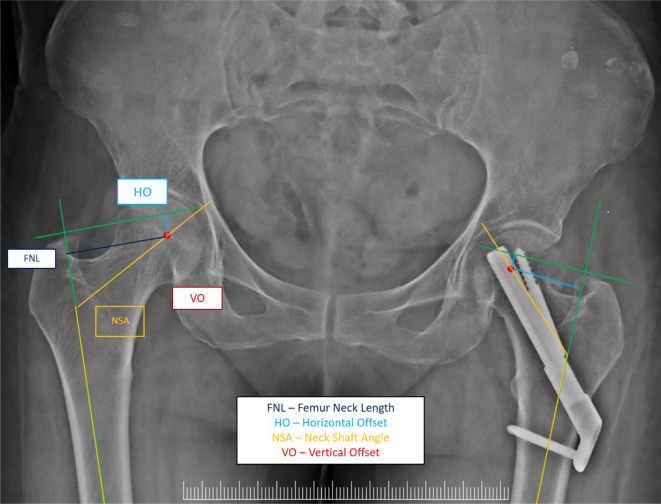

Purpose: Fracture union after osteosynthesis of a fracture neck femur (FNF) occurs by compression of the fracture ends and potential neck shortening. Selection of an implant for fixation of a femoral fracture of the neck can be challenging when making management decisions. Femoral neck shortening after internal fixation of FNFs using a femoral neck system (FNS) or multiple cannulated cancellous screws (MCS) was compared.

Materials and methods: This prospective interventional single-blinded randomized controlled trial was conducted at a university teaching hospital. Sixty patients undergoing internal fixation for management of sub-capital or trans-cervical FNFs were randomized and assigned, to one of the two groups-the test group (FNS group) and the control group (MCS group). Primary outcome was determined by measuring the difference in 1-year shortening of the femoral neck on radiographs between FNS and MCS. The secondary objective was to determine the correlation between neck shortening with patient reported outcome measures (PROMs) at the end of the final follow-up.